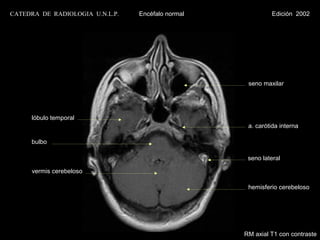

CATEDRA DE RADIOLOGIA U.N.L.P.   Encéfalo normal             Edición 2002

seno maxilar

clivus

a. carótida interna

bulbo

seno lateral

vermis cerebeloso

hemisferio cerebeloso

RM axial T1 con contraste